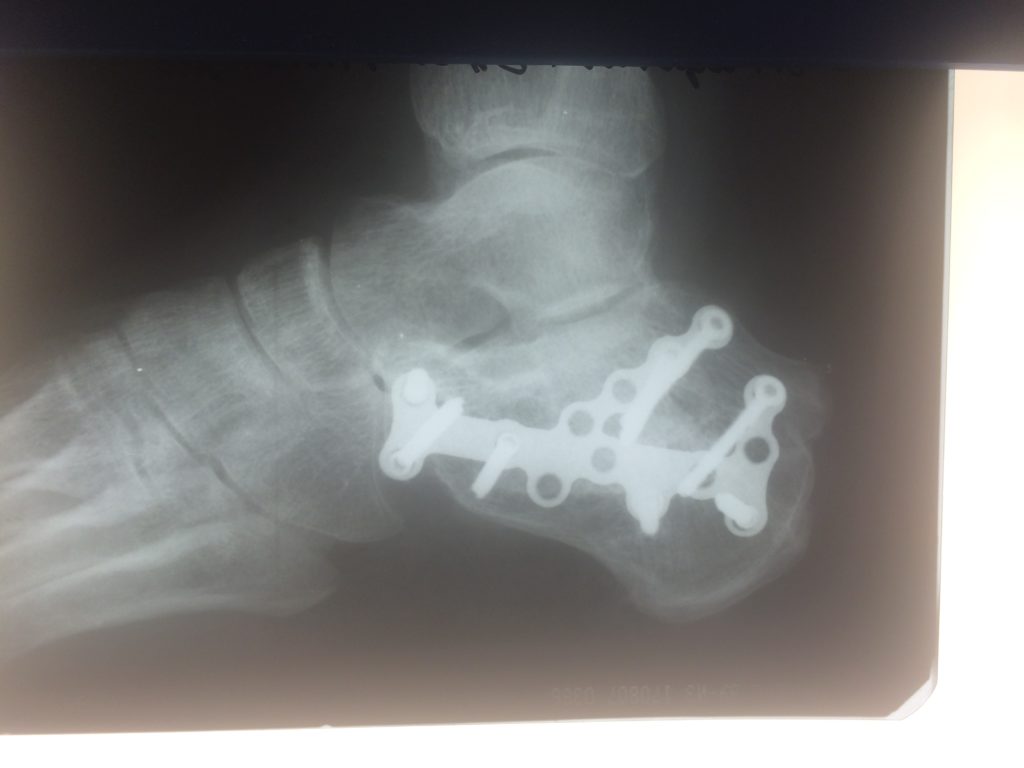

Операция – открытая репозиция, остеосинтез пяточной кости пластиной с костной ксенопластикой материалом «Остеоматрикс». На контрольных снимках в три месяца имеется консолидация перелома, миграции фиксатора нет, имеется остеоинтеграция ксенопластического материала.

Отдаленные результаты через 6 (шесть) месяцев: